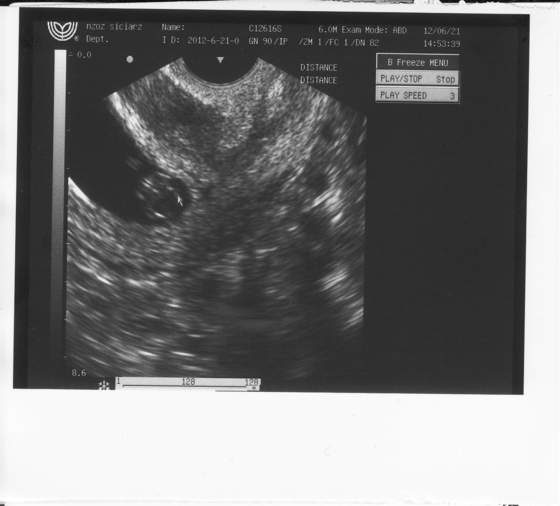

dotka no ciekawe czy to sie faktycznie sprawdzi hehhee, az sprawdzilam w mojej poprzedniej ksiązeczce ciązy z synkiem i faktycznie tętno miał również 170

m@linka po pierwsze nie zawsze lekarz mówi jakie jest tętno, chyba ze spytasz bo to jakie jest napewno widzi podczas badania, ale pewnie wszystko ok wiec jak nie spytalas to nie powiedzial, a po drugie ta przeziernosc karkową i nosek itd sprawdza sie dopiero po 12 tygodniu tzn zazwyczaj miedzy 12 a 13 tyg wtedy jest najodpowiedniejsza wielkosc malucha zeby mozna było to wszystko wyłapac takze sie nie denrwuj, a kiedy masz nastepną wizyte? Bo jesli nie w przaciagu 2-3 tyg to koniecznie idz gdzies prywatnie to sprawdzic, to jest jedno z najwazniejszych badac w czasie ciąży...